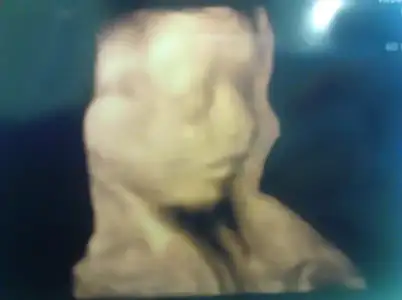

7 ekim sabah 09:00 şeker yüklemesi için randevu almış bulunmaktayım

tabiki minişimi de görcemmm![]()